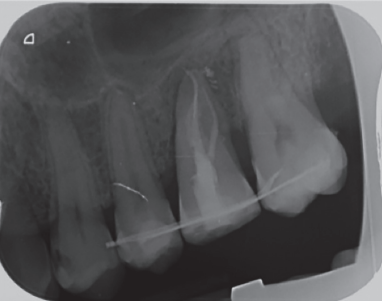

In the radiograph examination, through a panoramic radiograph, both lower third molars were seen retained in horizontal position (Figure 3), and apical radiolucent images in positions of 2.6 and 4.6. The cone beam scan evaluated the root morphology of the left upper third molar and the size of the apical radiolucent lesion of the left upper first molar (Figure 4), necessary data to assess the degree of adaptation of the donor tooth in the recipient bed.

associated with the root remains of 2.6 and the conical root of 2.8 are seen.

The published clinical studies evaluate patients clinically and radiographically, by periapical radiographs9,10,12,15,17,18 or by periapical and panoramic radiographs4,13,14. The periapical radiography shows the presence of radiolucent areas, external and internal root resorptions, ankylosis and the state of root development18, being fundamental in the evolution of this therapeutic modality. In the present clinical case, a radiolucent area around the tooth was radiographically visible, which was modified over time, to achieve a similar bone density of the bone in contact with the transplanted tooth, compared to the surrounding bone. Additionally, no apical lesions or root resorption were observed during the followup period.